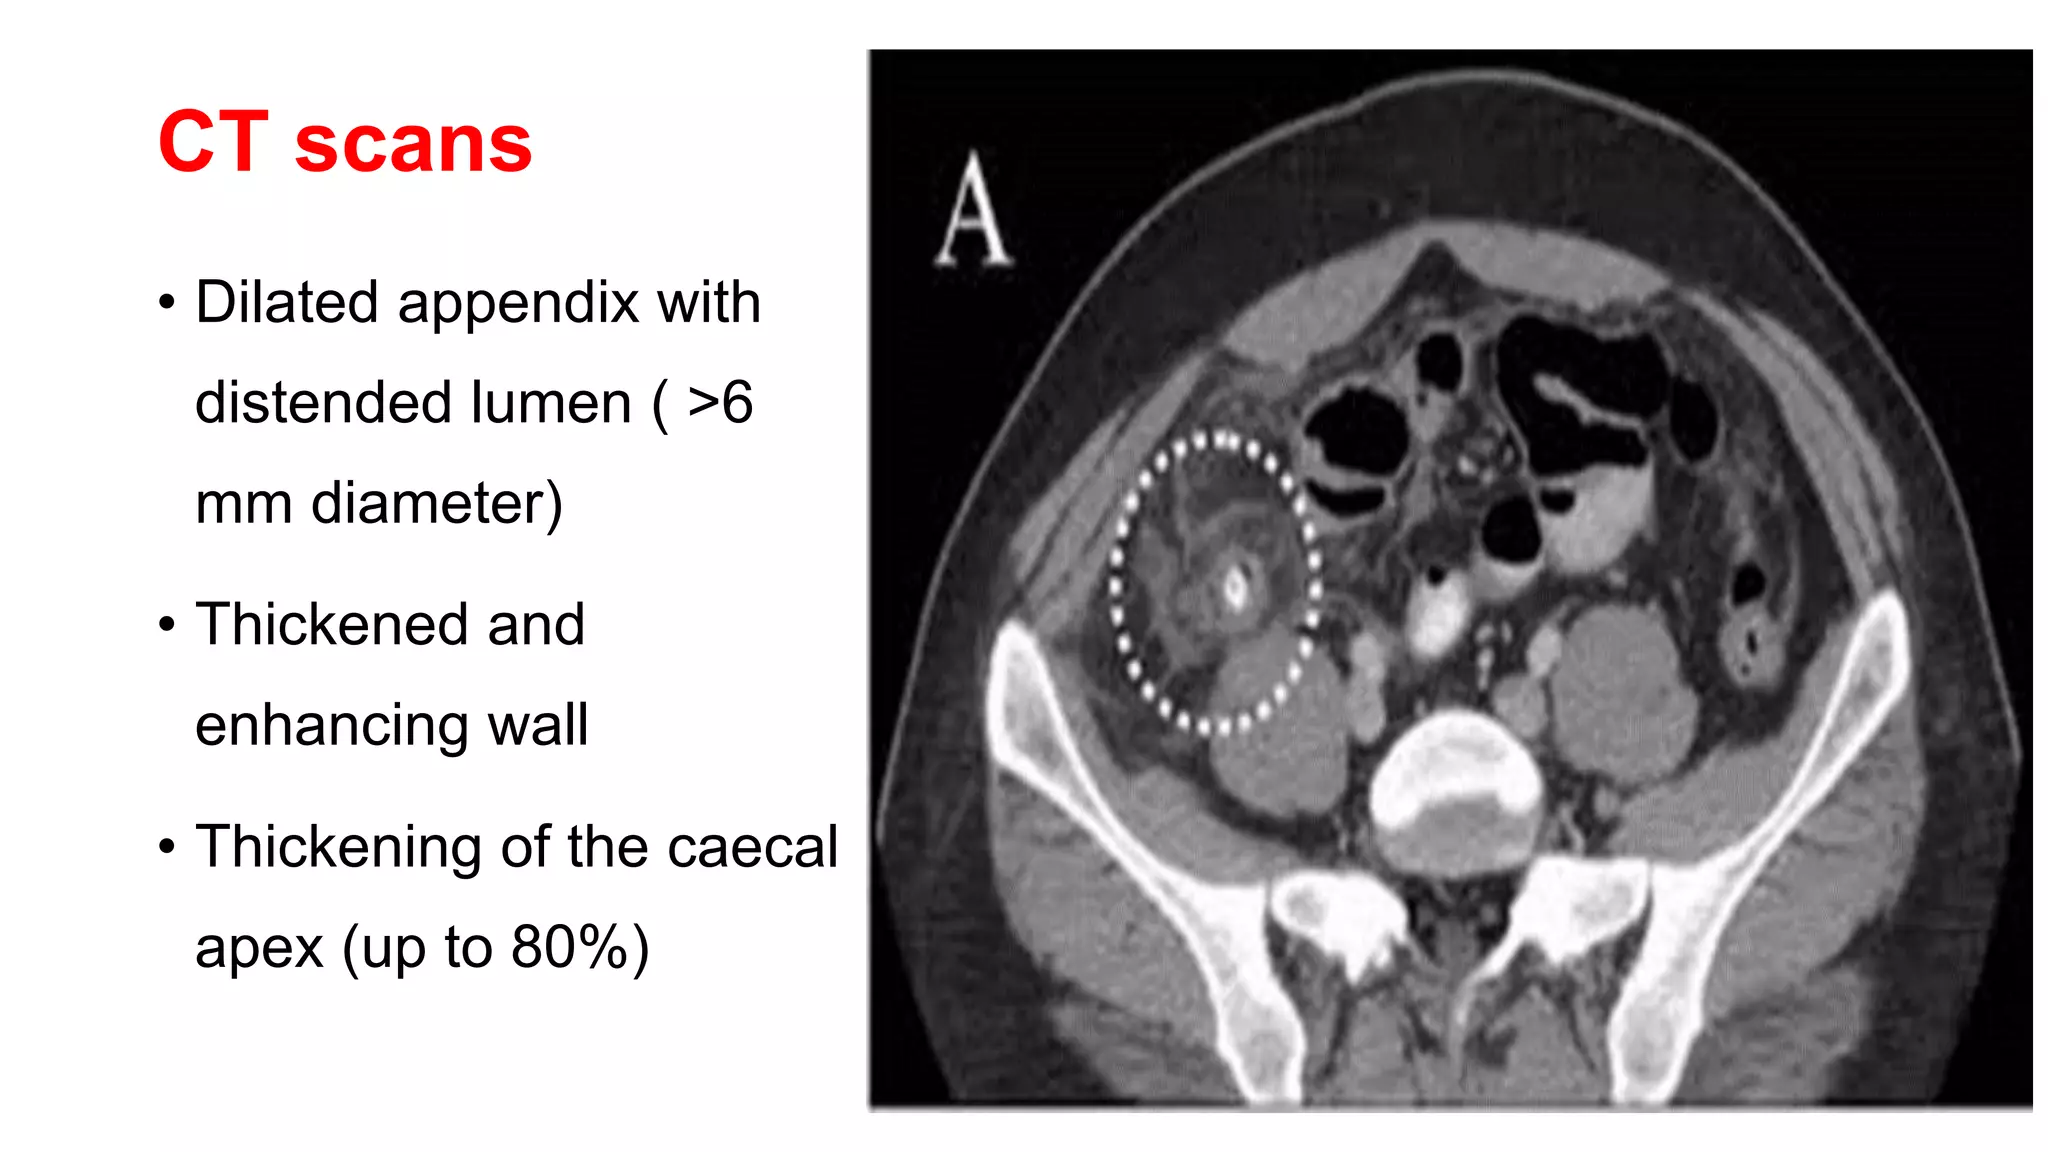

Abdominal pelvis CT scan. a Initial CT scan showing dilated appendix ...

Axial CT image shows dilated appendix lumen filled with fluid, with ...

CT image of acute appendicitis without perforation. The dilated ...